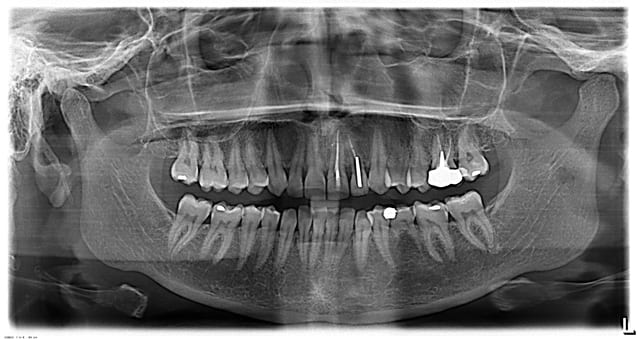

je vous poste cette pano car je sèche concernant le diagnostic,

patiente 34 ans, pas d'antécédents,

douleur quasi continue coté droit, sous l'oreille et le long

du bord inf de la branche montante de la mandibule,

légèrement douloureux à la palpation,

voyez-vous un problème osseux à la pano ?

une idée de l'origine des douleurs ?

Mastication unilatérale droite, vu l'état à gauche...

virer la 75 et implant, 36 dentinite, revoir peut-être le traitement et la k sur 26...

La pano est relativement pourrie mais tu es peut-être chanceux. Je ferai un scan cervico-facial en premier.

J'adresserai ensuite le patient à un chirurgien cervico-facial pour avis et ablation d'un processus styloïde apparemment très long et qui bien très bien visible sur cette pano malgré tous les défauts qu'elle comporte.

La sémiologie clinique peut tout à fait coller.

- Syndrome d'Eagle possible mais toute apophyse styloïde longue (4% de la population) n’entraîne pas forcément le syndrome. Rechercher si la déglutition et la rotation du cou est sensible.

- DAM possible mais en l'absence de bruit articulaire on est sur du musculaire donc assez rarement unilatéral et surtout sans accompagnement de douleur du temporal.

- problème parotidien (l'image de calcification autour de l'apophyse styloïde est bizarre)

J'adresserai volontiers à un orl après avoir demandé un scan.